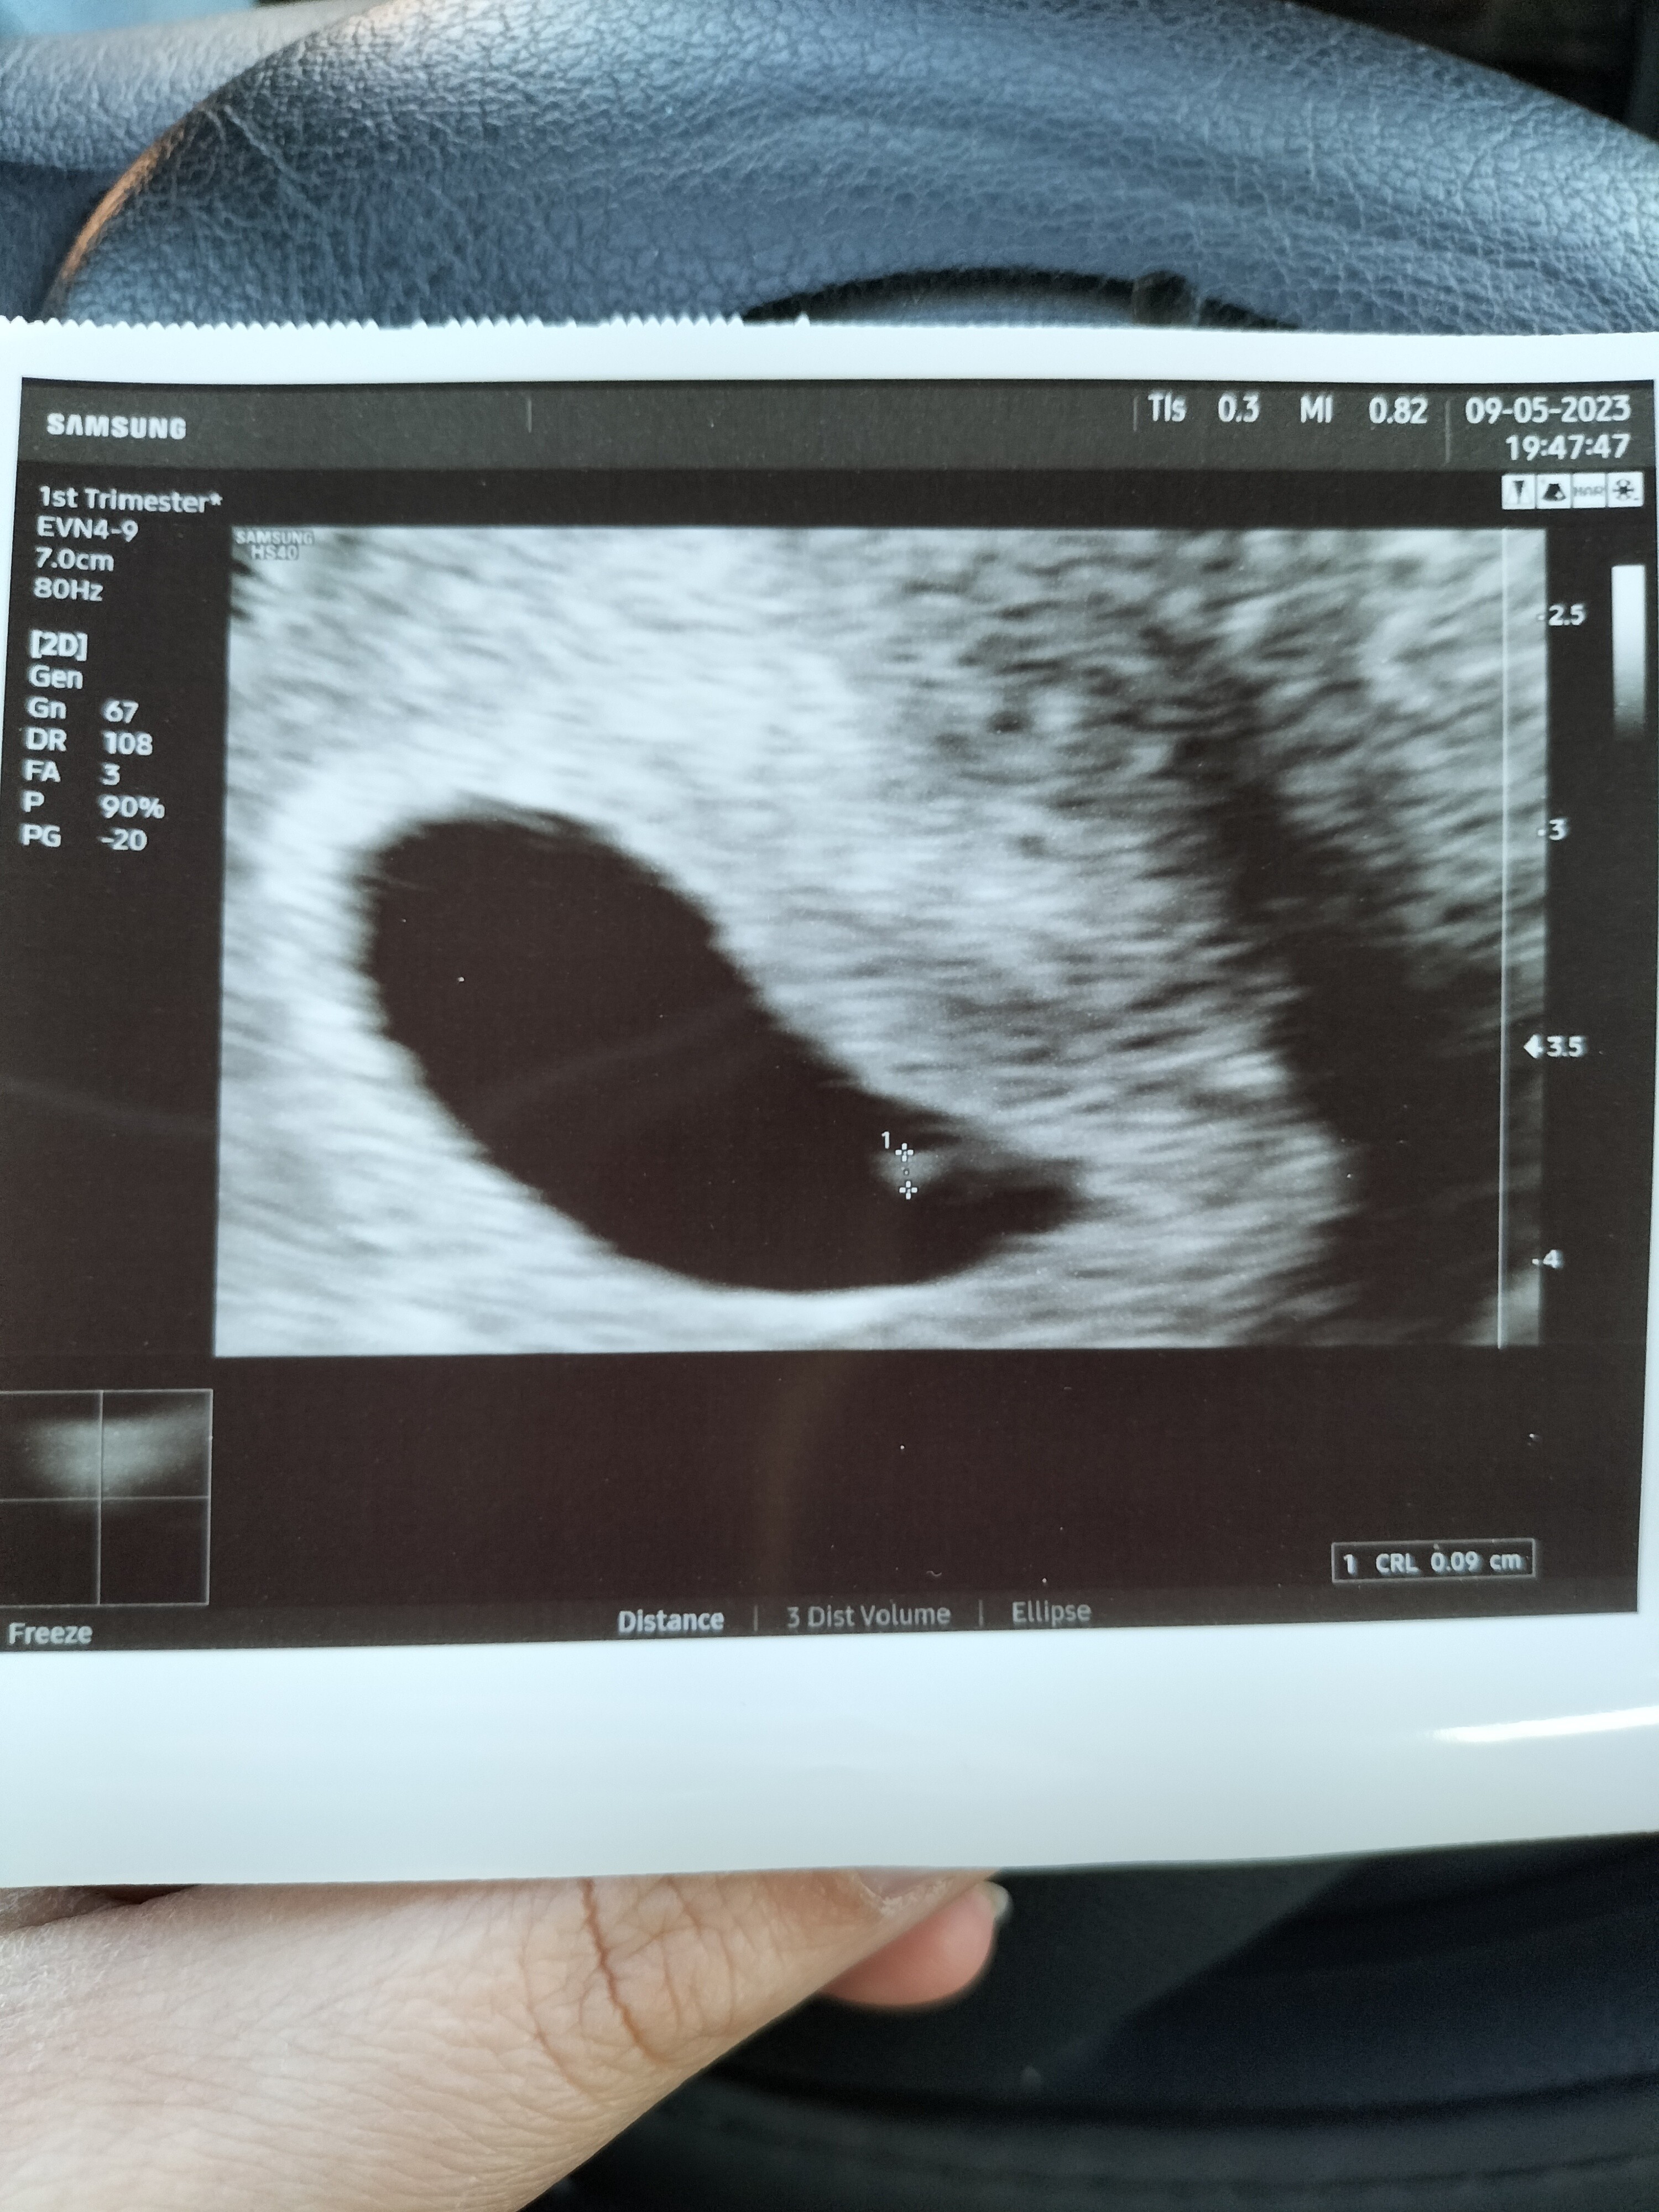

Boziu tej kropceczce już bije serduszko?Właśnie wyszłamjest Człowiek maleńki

serduszko juz bije

wyniki dobre kolejna wizyta 18.05.

Załączam pierwsze zdjęcie nowego Człowiekapiękny prawda